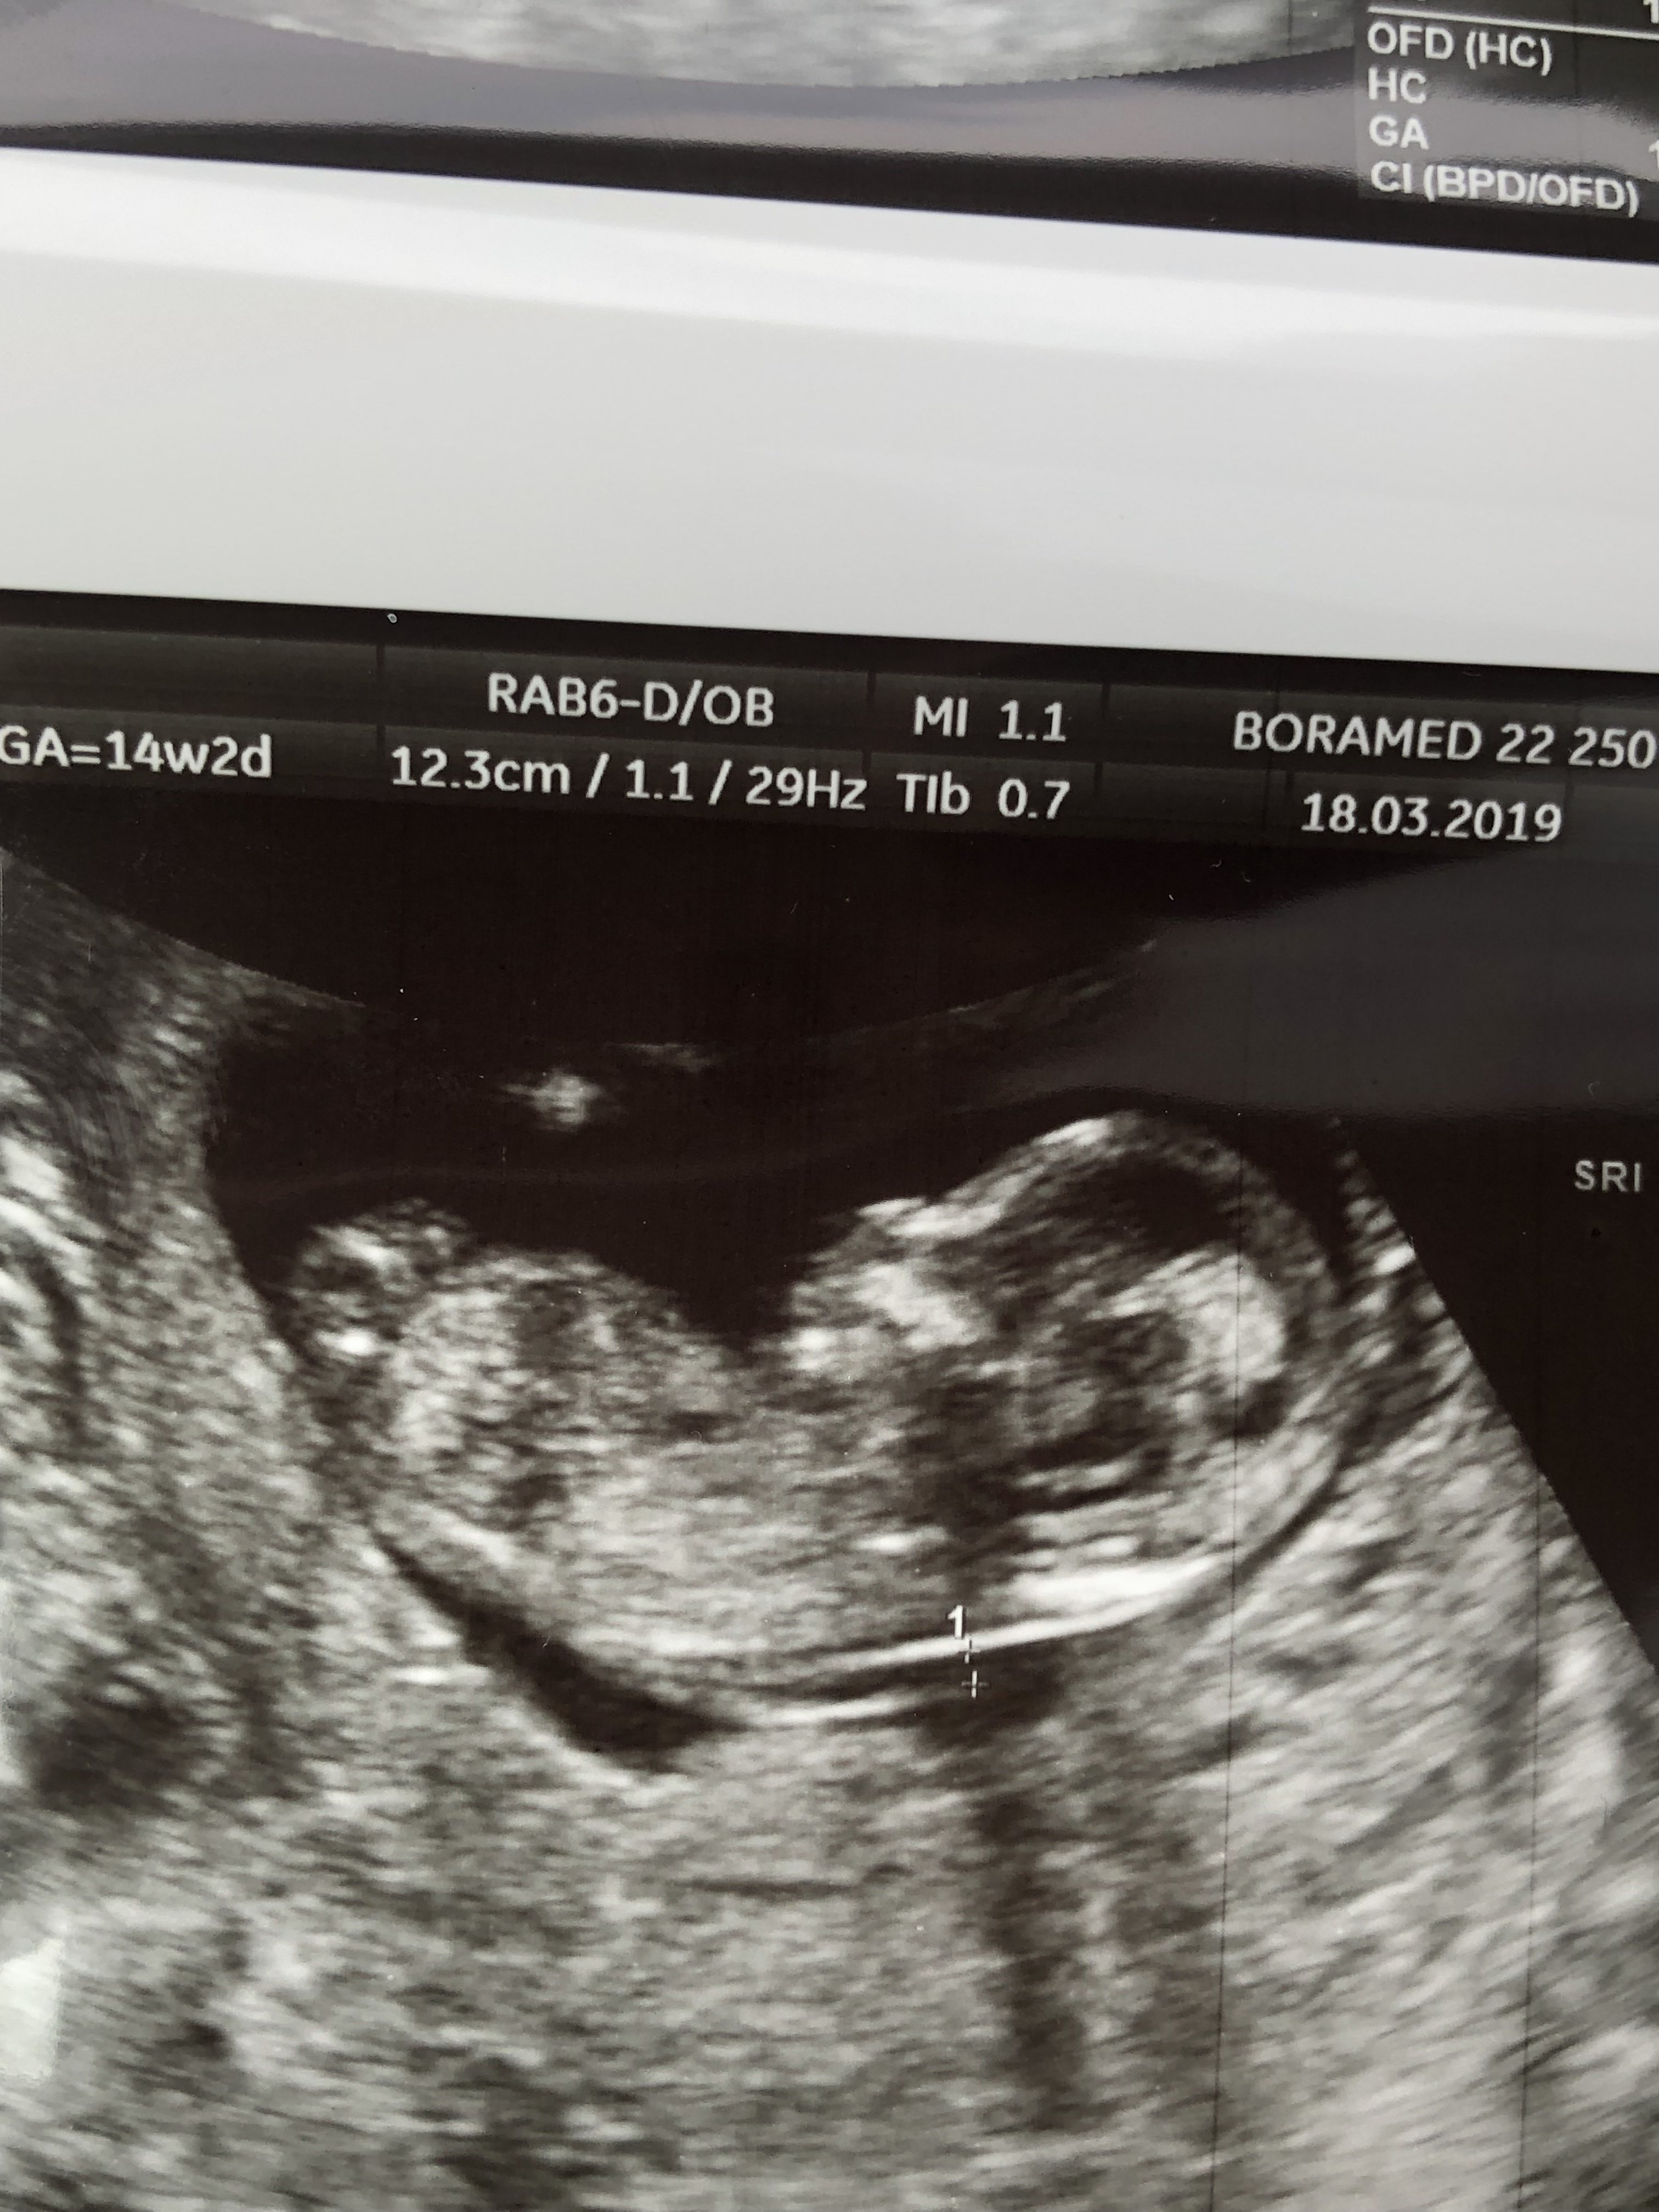

Cześć dziewczyny proszę was o ocenę zdjęcia usg... Miesiąc temu zapowiedzieli mi syna a 4 grudnia na połówkowym ze córka... Trochę mam mętlik w głowie 😞

I czy ten „cypelek”na nubie o czymś świadczy czy maja go zarówno chłopcy jak i dziewczynki

Zżera mnie ciekawość, choć gdzieś w środku czuje ze druga córa się szykuje zamiast synka...

• E622F8B3-4E12-4F76-A34E-879251B1E76F.jpeg

E622F8B3-4E12-4F76-A34E-879251B1E76F.jpeg

295,3 KB · Wyświetleń: 416